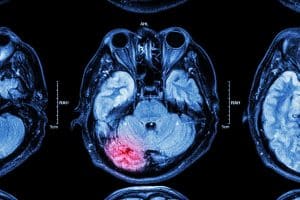

A diffuse axonal brain injury (DAI) is a severe form of traumatic brain injury (TBI) characterized by widespread damage to the brain’s nerve fibers, known as axons. It typically occurs when the brain is subjected to rapid stop and go forces, often seen in car accidents or severe falls. DAI can lead to a range of neurological and cognitive deficits because it affects multiple areas of the brain. The injury disrupts the communication between brain cells, resulting in a variety of physical, cognitive, and emotional symptoms, which can be both immediate and long-lasting. Treatment and recovery from DAI can be challenging, and it often requires extensive rehabilitation and medical care.

DAI is typically diagnosed clinically. Doctors often consider diffuse axonal brain injury when a patient has a low score on the Glasgow Coma Scale (GCS) for an extended period (usually over six hours). GCS is a tool used to evaluate a person’s level of consciousness and neurological functioning after a head injury or other medical emergencies. It assigns a score based on a person’s ability to open their eyes, respond to verbal commands, and move purposefully, with a lower score indicating more severe impairment of consciousness.

The severity of DAI determines how patients present. For example, mild DAI can look like a concussion, with symptoms like headaches, dizziness, nausea, vomiting, and fatigue. Severe DAI can result in loss of consciousness and a persistent vegetative state, with only a few patients recovering consciousness in the first year after the injury. Some patients also experience dysautonomia, which includes symptoms like fast heart rate, rapid breathing, sweating, low blood pressure, high body temperature, abnormal muscle tone, and unusual body postures.